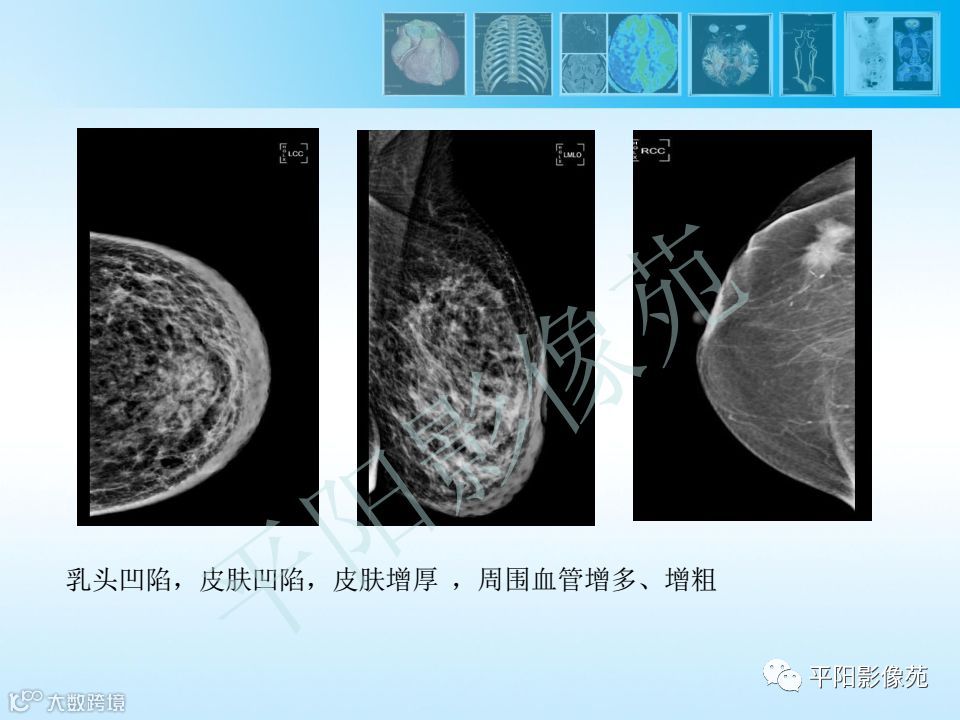

乳腺钼靶报告书写规范

乳腺钼靶报告书写规范 平阳影像苑